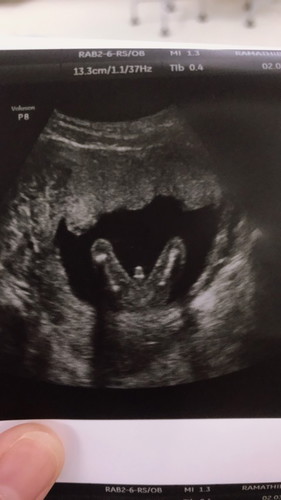

แบบนี้ ชายหรือหญิงคะ

แบบนี้ ชายหรือหญิง คะ